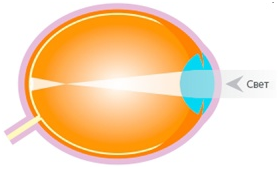

Суть проблемы в схемах

На второй схеме представлено миопическое глазное яблоко: по мере роста длины глаза миопия прогрессирует, и зрение вдаль становится все более нечетким.